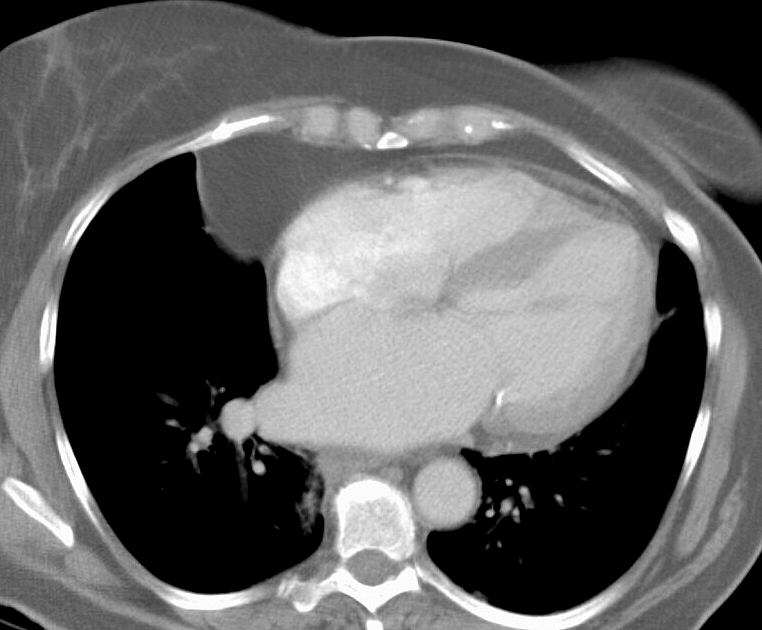

Fat Pad

Case 7b